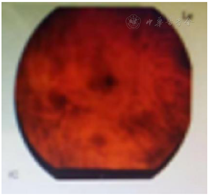

患者于2020年3月10日因"发热伴双眼肿痛2 d"再次入住我科,入院2 d前无明显诱因下出现发热,体温高达39.3℃,伴双眼肿痛流泪,左眼肿痛较重,伴失明。入院查血常规示WBC 57.83×109/L,MONO 11.65×109/L,RBC 3.87×109/L,HB 64 g/L,HCT 0.334,PLT 345×109/L,CRP:85.22 mg/L。C反应蛋白凝血系列未见明显异常。心脏超声示无明显积液。阳性体征:双眼结膜充血,脾肋下可触及。眼科会诊后完善眼底镜等相关检查诊断虹膜睫状体炎,双眼眼底出血(图3)。眼底分泌物进行镜检发现有大量单核细胞,考虑CMML肿瘤细胞浸润可能,遵眼科医嘱消炎对症治疗,2020年3月15日再次行阿扎胞苷100 mg qd d1~7去甲基化治疗后复查视力明显好转后出院。